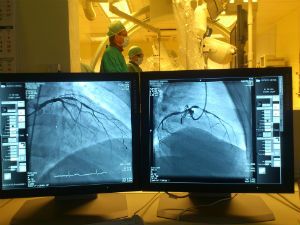

Коронарная ангиография – это инвазивный (внутренний) вид исследования состояния сосудов сердечной мышцы, с помощью которого можно диагностировать ишемическую болезнь. В момент осуществления манипуляции пациенту в паховую или лучевую артерию вводится контрастное вещество, распознающееся рентгеновскими лучами. Общий вид исследуемых сосудов при просвечивании рентгена выводится на монитор специальной компьютерной техники.

Рентгеноперационная – это помещение, где в стерильных условиях при помощи рентгеновского оборудования врачи выполняют внутрисердечные исследования и лечение. Именно рентген позволяет доктору во время всей процедуры видеть сердце, коронарные артерии.

- Врач катетером встает прямо в устья венечных артерий. На другом конце (где вошли через кожу) к катетеру присоединен шприц с контрастом. Вот его и вводят. Контраст заполняет сердечные артерии и смывается током крови. В течение всей процедуры идет видеозапись. Врач наблюдает за ходом процесса на экране. Монитор можно повернуть так, чтобы пациент тоже увидел собственные артерии. Вы сможете беседовать с доктором. Через катетер хирург вводит контраст из шприца. Нажмите на фото, чтобы увидеть его в четком варианте Врач наблюдает за ходом процесса на экране